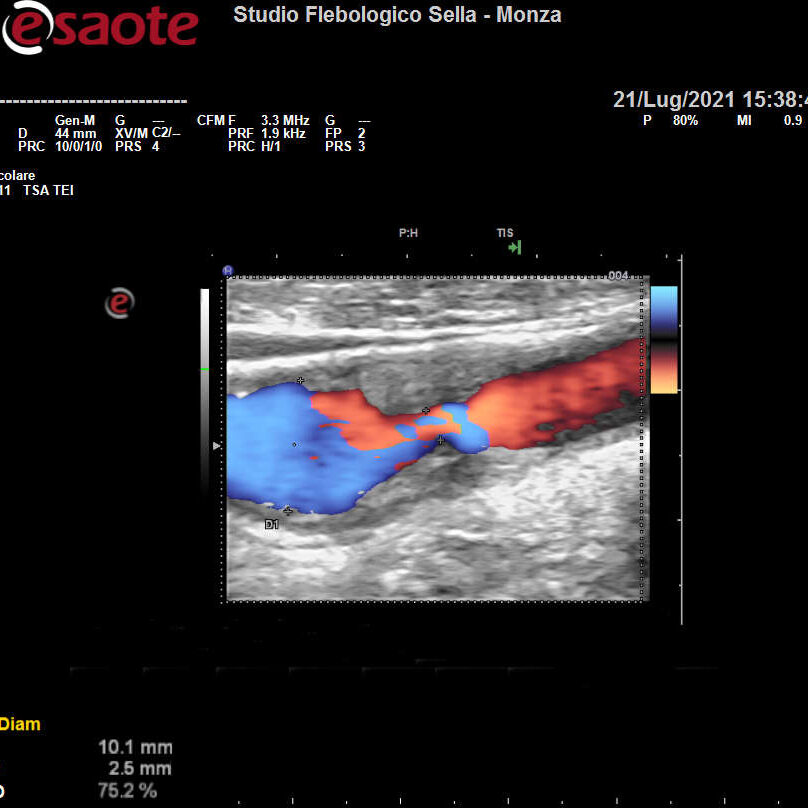

Abbiamo precedentemente visto come l’intuizione del fisico austriaco Christian Doppler ha posto le basi teoriche per la nascita dell’EcocolorDoppler. La deformazione degli ultrasuoni nell’attraversare il corpo umano consente la ricostruzione in immagini dei tessuti, vasi compresi. Otteniamo quindi informazioni sulla forma e il decorso dei distretti vascolari esplorati e sulla velocità del sangue contenuto. Un utile campo applicativo è rappresentato dall’EcocolorDoppler dei tronchi sovraortici ossia lo studio delle arterie del collo. Il precoce riscontro di problemi a carico di carotidi e vertebrali ne previene infatti una grave complicanza: l’ictus ischemico.